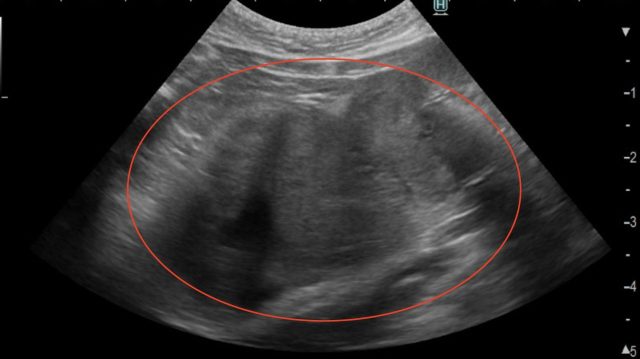

膵腺癌の超音波画像(赤丸)